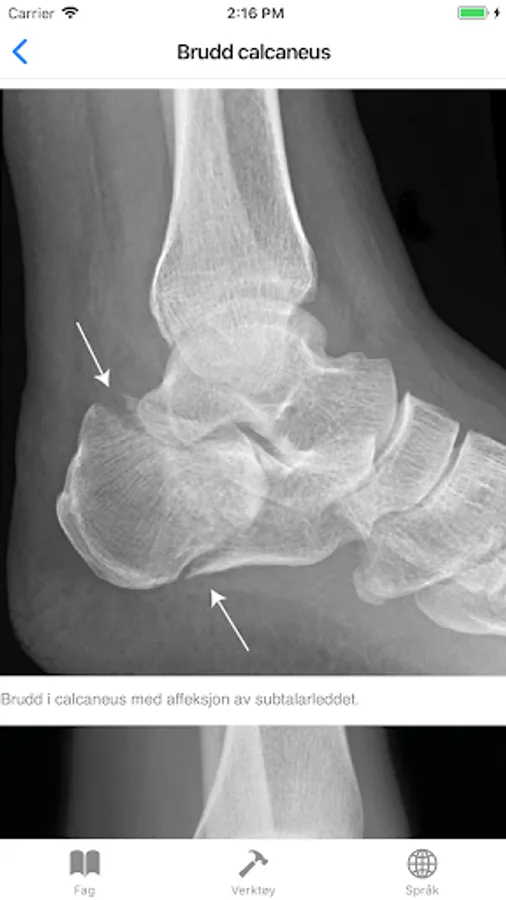

Calcaneus fracture